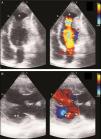

Case reportA 29-year-old woman presented with easy fatigability and chest discomfort for several months. These symptoms were insidious in onset and progressed little. There was no history of palpitations, syncope or dyspnea. She was hemodynamically stable with diffuse apex beat shifted downward and outward. The chest radiograph showed calcified LV apical and basal aneurysms. The electrocardiogram showed no pathological Q waves and normal precordial R-wave progression (Figure 1). Two-dimensional transthoracic echocardiography (iE33 xMATRIX, Philips Healthcare, Andover, MA, USA) showed moderate LV dysfunction; multiple LVAs (large apical aneurysm, moderate sized submitral aneurysm, and basal anterior aneurysm); normal contractility of the rest of the LV wall; and normal valves, other chambers and great vessels (Figure 2). The echocardiogram showed continuity of the myocardium of the aneurysms with the rest of the myocardium. Color flow Doppler showed flow in and out of the aneurysms.

LVAs have been depicted and characterized by various imaging modalities.3 Radionuclide ventriculography and echocardiography can demonstrate LVAs more readily.1 A definitive diagnosis of LVA is best made non-invasively by echocardiography, which also helps in distinguishing a true from a pseudoaneurysm based on the demonstration of a narrow neck in relation to cavity size in the latter.27 The myocardium surrounding a true aneurysm is in continuity with the rest of the myocardium, as in our case, while there is no myocardium around a pseudoaneurysm, leading to a breach in the continuity of the normal myocardium.28 An abrupt discontinuity of the endocardial image between the aneurysm and adjacent normal myocardium is a characteristic finding with a pseudoaneurysm.14 True and pseudoaneurysms can both be non-contractile or dyskinetic and may contain thrombus.28,29 Color flow Doppler is useful in establishing the diagnosis as flow in and out of the aneurysm, as well as abnormal flow within it, can be detected. Pulsed Doppler imaging can reveal a to-and-fro pattern with characteristic respiratory variation in peak systolic velocity.1 However, echocardiography has the limitation of occasional failure to define the neck.30